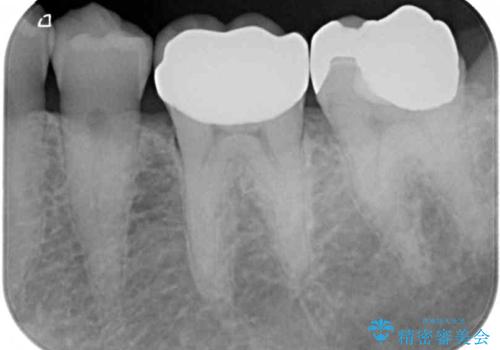

- 奥歯が欠けており、近医でむし歯を指摘されたとのことで来院された患者様です。

1番奥の歯はゴールドインレー周りがむし歯で欠けており、手前の歯はインレーの下にむし歯がある状態でした。

1番奥は歯肉に覆われている部分が大きいため、欠損部とむし歯の部分をゴールドインレーにて修復し、手前の歯はオールセラミッククラウンにて補綴治療を行うこととしました。